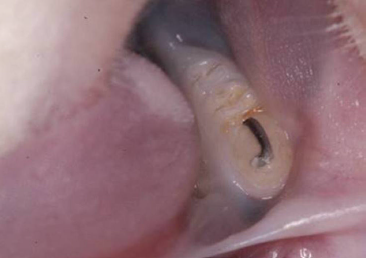

The cuts were stained with hematoxylin and eosin according to the routine protocol used at the Histologic Laboratory of the Universidade do Sagrado Coração. Three equidistant histologic sections were selected per tooth for the histometric analysis. The sections were digitalized at 100× magnification (10× objective lens and 10× ocular lens). Using the linear measuring system (Image-Pro®, Media Cybernetics, Silver Spring, MD, USA), we measured the distance from the free gingival margin (FGM) to the cemento-enamel junction (CEJ) to evaluate the gingival recession, and, also, the distance from CEJ to the reminiscent alveolar crest (Fig. 2). The measures were carried out on the mesial surface of the mandibular first molar and they were expressed in micrometers (μm).

In this experiment, no significant difference was observed between the OT (464.7 ± 116.04) and the CG (527.2 ± 97.19) (P = 0.192) groups when the CEJ–FGM distance was evaluated after 14 days (Fig. 3). These data show that the OT model failed to promote gingival recession in the OT group after 14 days.